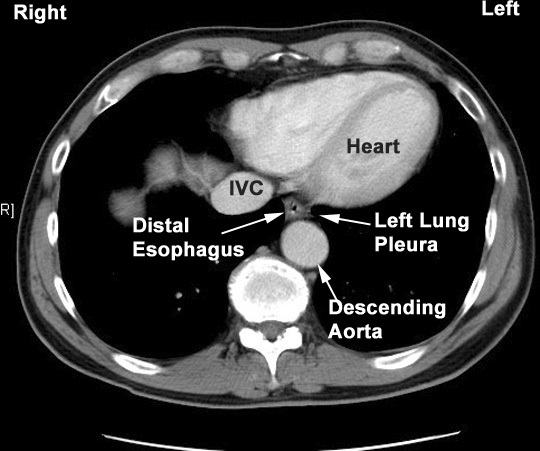

Diagram Of Esophagus Bronchi